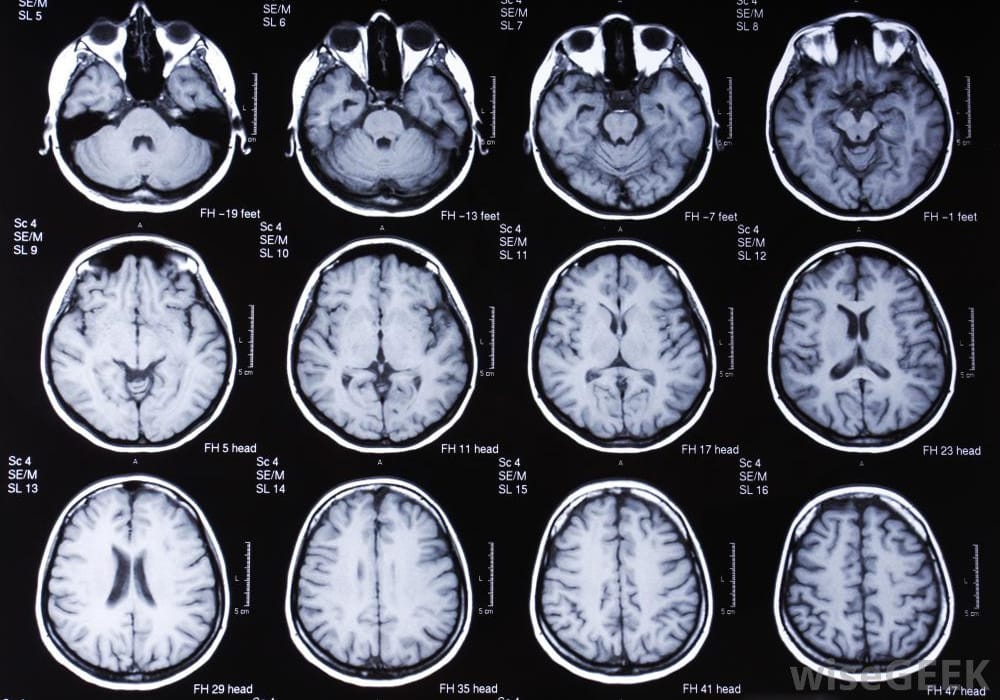

Нейровизуализация

МРТ и КТ головного мозга: Эти методы помогают исключить другие заболевания, которые могут вызывать симптомы, схожие с паркинсонизмом — например, опухоли, последствия инсульта или структурные аномалии.

DaT SCAN (СПЕКТ или ПЭТ): Специальное сканирование, позволяющее оценить состояние дофаминергических нейронов. Исследование помогает подтвердить диагноз болезнь Паркинсона на ранней стадии, особенно если клинические проявления не дают однозначной картины.